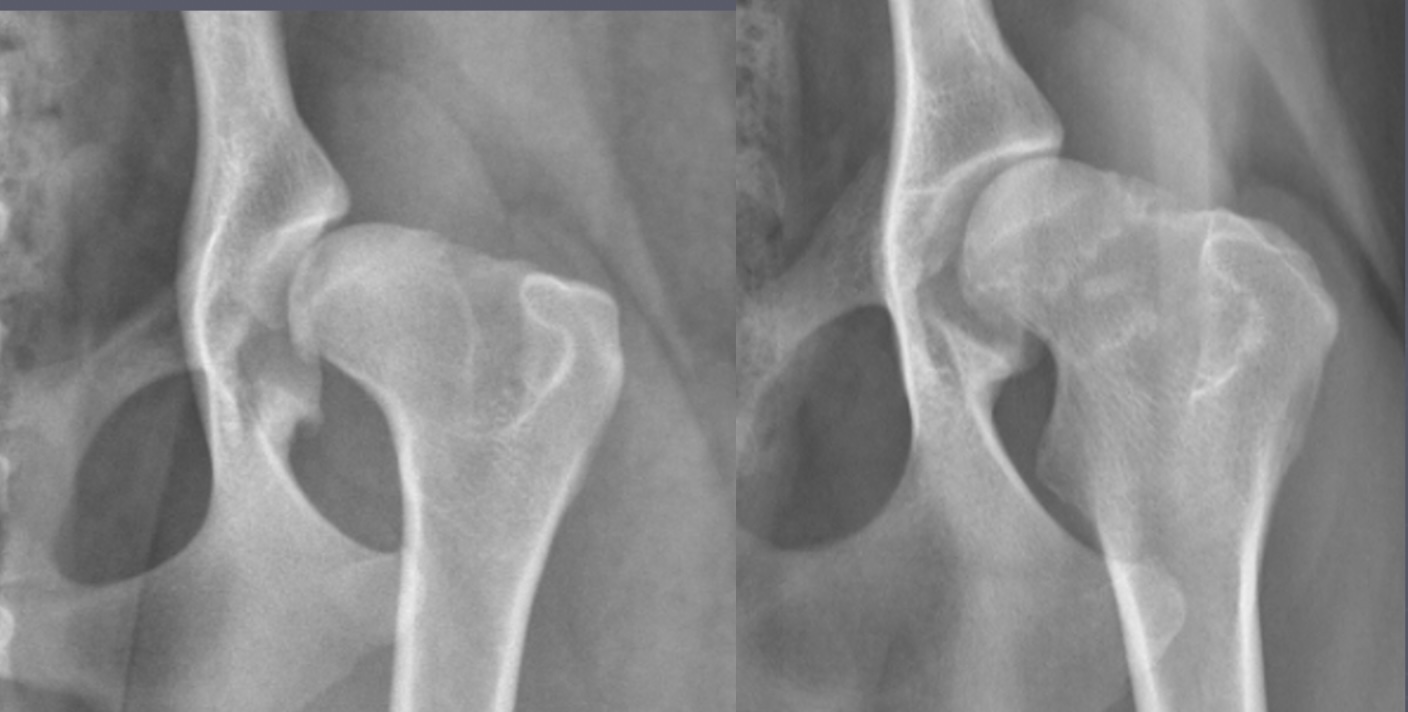

calve legg perthes signalment

immature toy/small dogs

unilateral

increased joint space, irregular femoral head

calve legg perthes